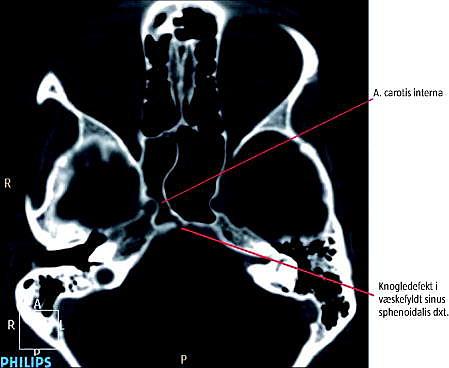

Ved en computertomografi (1-mm-snit) af ansigtsskelettet blev der påvist en 2-mm-knogledefekt.